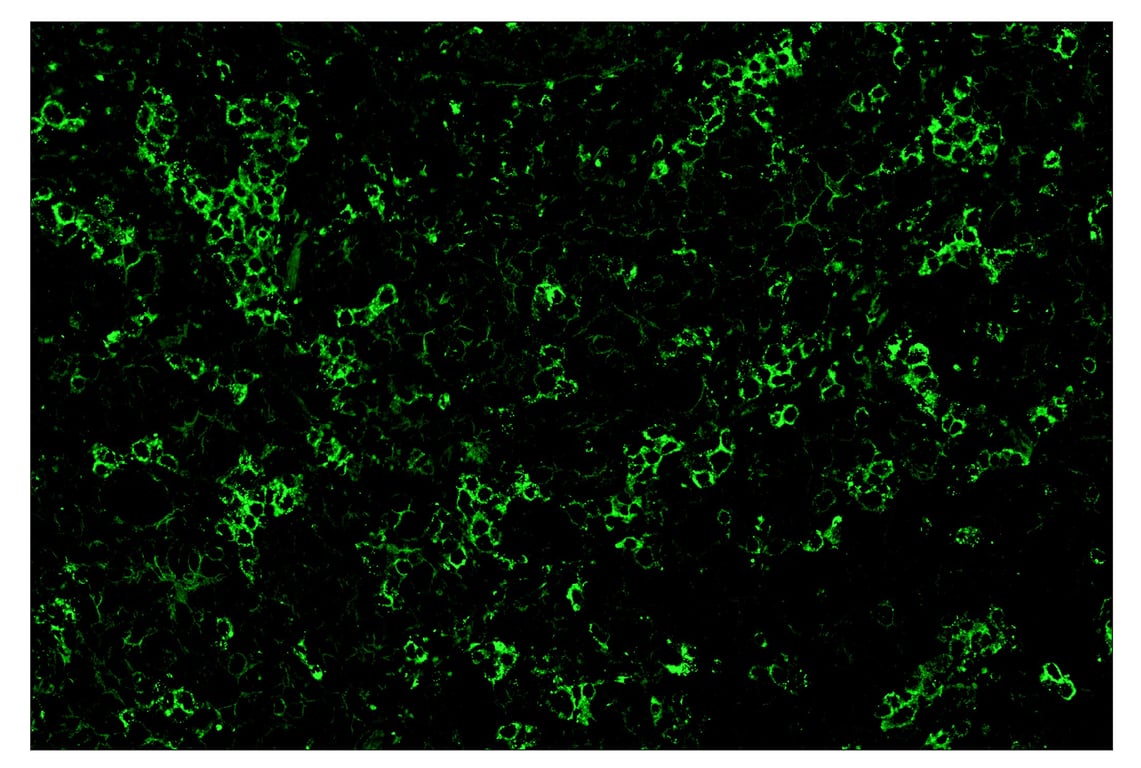

Immunohistochemistry Image 1: TIM-3 (D5D5R<sup>™</sup>) & CO-0010-750 SignalStar<sup>™</sup> Oligo-Antibody Pair

SignalStar™ immunohistochemical analysis of paraffin-embedded human non-small cell lung carcinoma using TIM-3 (D5D5R™) & CO-00010-488 SignalStar™ Oligo-Antibody Pair #81365 (green). All fluorophores have been assigned a pseudocolor, as indicated. Staining was performed on the BOND RX by Leica Biosystems.